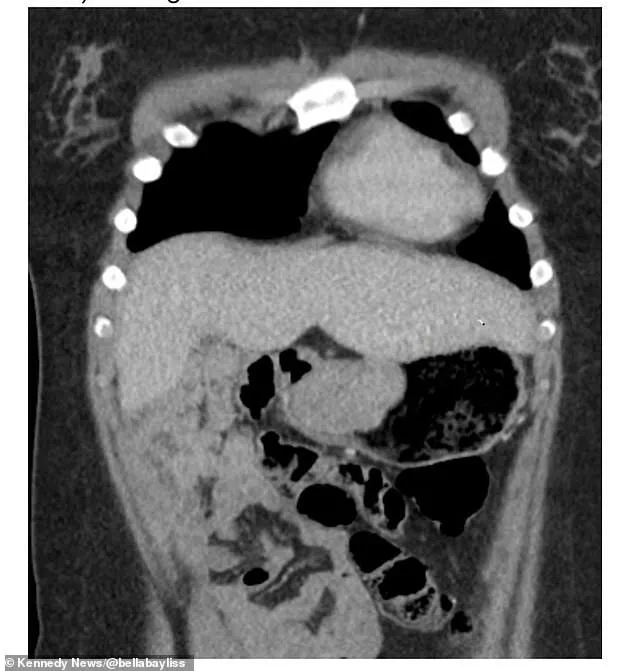

The results were shocking. 'They found a 6cm gastrointestinal tumour (GIST) in my stomach,' she said.

GIST, or gastrointestinal stromal tumors, affects only 10-15 people per million annually, making up one to two percent of all gastrointestinal cancers.

These tumors are caused by a sarcoma, a type of cancer that typically begins in bone or soft tissue but, in Bella's case, had developed in her digestive system.

Bella's doctors had to remove 70 percent of her stomach to excise the cancerous mass, a decision she believes could have been avoided if her initial concerns had been taken seriously. 'If they hadn't left me for so long, I wouldn't have had to have that much of my stomach removed because the tumour got bigger within that time,' she said.